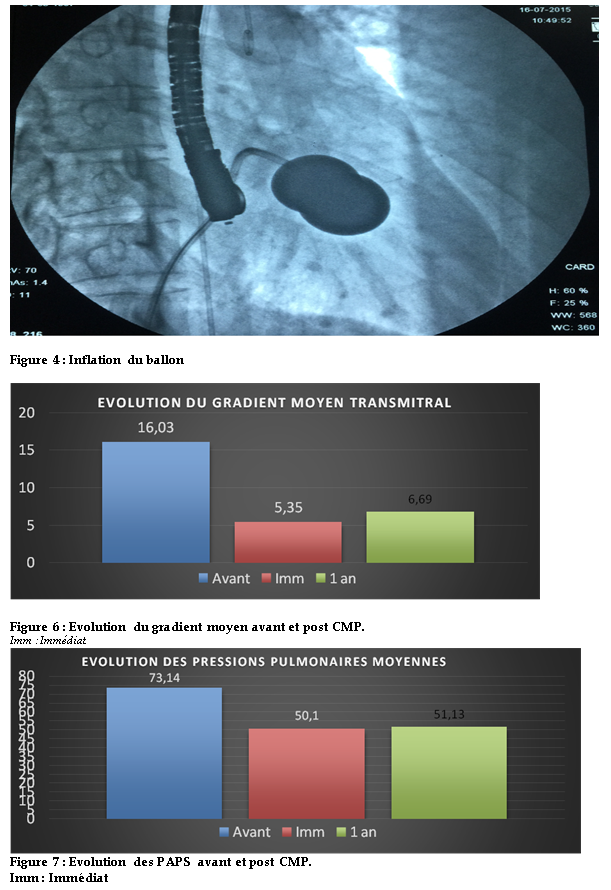

L’estimation par échocardiographie Doppler du gradient moyen montrait que le GM passait de 16,03 ± 6,83 mmHg à 5,35 mmHg ± 2,03 (p=1.714e-07) (fig6).

A l’écho-Doppler post-procédure, on notait une diminution des pressions pulmonaires (PAPS) évaluées par le flux d’insuffisance tricuspide de 73,14 mmHg ± 26,86 à 50,1 mmHg ± 18,5 (p=2.672e-06).La figure 3 illustre les courbes des PAPS avant et après dilatation.

Figure 1 : Mesures échographiques de la surface mitrale et du gradient Trans mitral